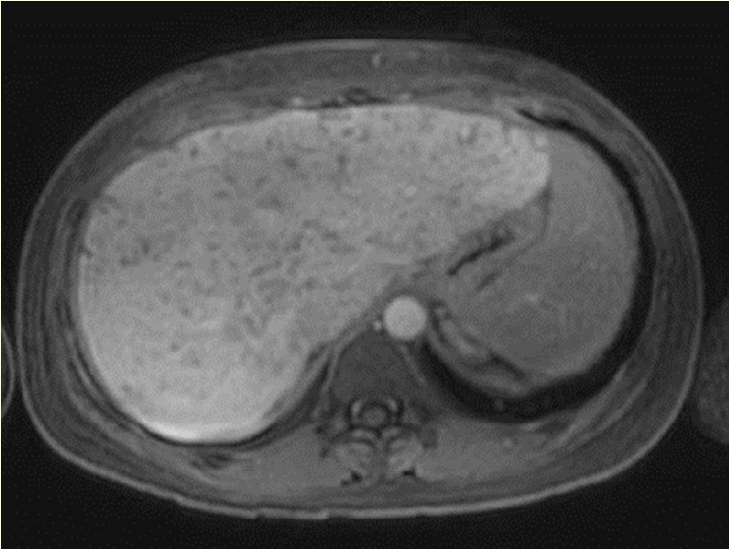

Herpetic Hepatitis Resolution in an Immunocompetent Patient After Early Treatment with Acyclovir

Fernanda Cruz-Nunes, Vivian Rotman, Klaus Steinbrück, Reinaldo Fernandes and Rodrigo Luz. 9(11): 13-16.